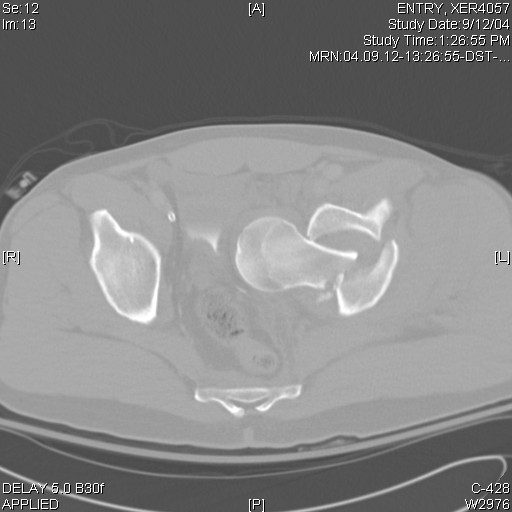

Intrapelvic farcture dislocation of the hip

Anyone ever seen one like this before? Any suggestions on how to get that thing out of there,because I tried and couldn't

-got called in to the OR by a colleague with the patient already on the fracture table and 2 big incisions (lateral and iliac crest) already made. Gave up after an hour or two and will try again if I can figure the solution.

Yes. We used a Watson-Jones exposure, spread the acetabular fracture with a laminar spreader, and used a Schanz pin to remove the proximal femoral fragment, then fixed it, and later fixed the acetabular fracture.

I have had one very similar. I placed him lateral decubitus, did a posterior approach, and did similar to what Chip described. The posterior approach allowed me to fix what appears to be a transverse acetabular fracture. The femoral neck can be fixated from that approach with multiple screws, although there may be more there than "just" a neck fx. The patient later required hemiarthroplasty for total head osteonecrosis.